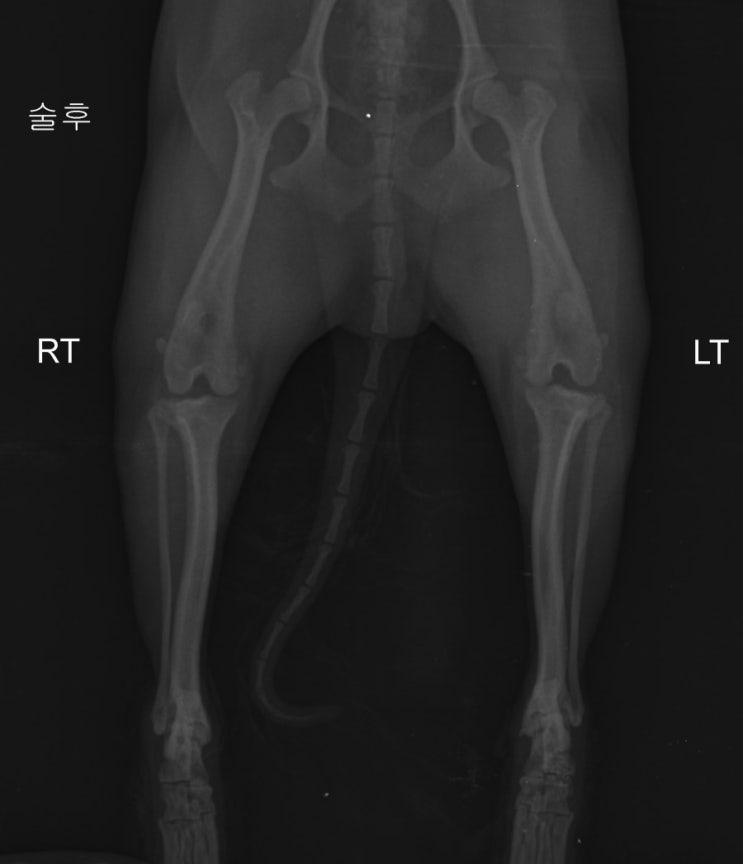

수술후.

수술후 한달까진 평가를 주기적으로!! 아주 잘 유지되고 있네요.